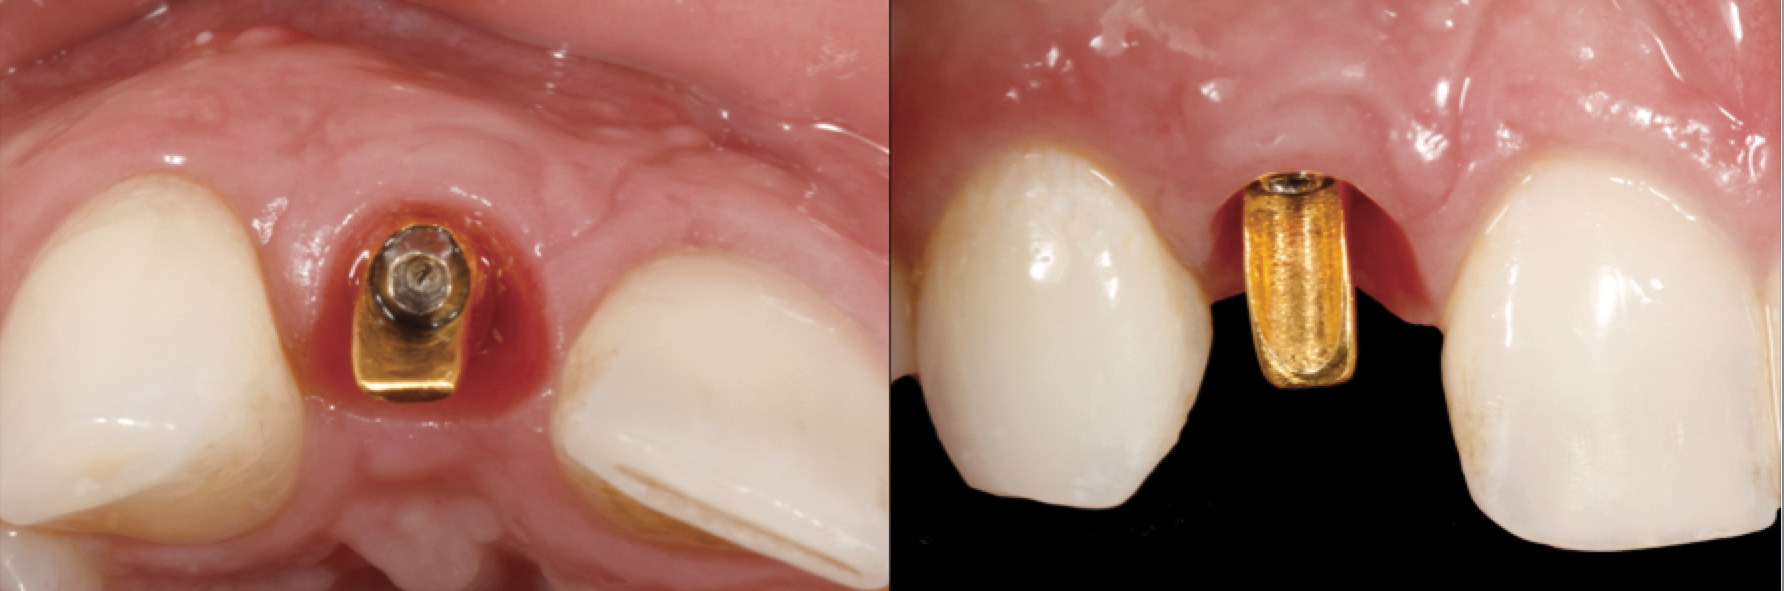

The following case report provides an example of this case scenario: A 24-year-old white male presented with congenitally missing tooth No. 26 restored with a single-tooth cement-retained implant restoration. The implant was placed excessively to the facial aspect of the edentulous site and too shallow, and the periodontal phenotype was thin scalloped (Figure 32). In an effort to mimic the lost midfacial soft tissues, pink ceramics were used as a cosmetic facade. Even though the restoration was not in the esthetic zone, the patient was highly displeased with the esthetic outcome and sought remediation.

The crown and screw-retained custom abutment were removed, and a surgical cover screw was placed into the implant, thereby allowing spontaneous gingival augmentation in situ (Figure 33 and Figure 34). Note that the lingual aspect of the implant site was significantly more coronal than the labial aspect, which was positive because the defect would be limited to a facial–lingual defect. A fixed RBR bridge was cemented on the adjacent teeth and used as a tooth-supported transitional provisional restoration (Figure 35). A few weeks were allotted to let the soft tissue heal and migrate around the cover screw (Figure 36) to see if there would be complete coverage, thereby allowing a soft-tissue augmentation procedure to be performed with primary flap closure as in clinical scenario No. 2. The major obstacle in achieving a positive tissue response was that the implant depth was also deficient because the implant–abutment connection was at the level of the free gingival margin. It was decided that the best treatment option would be to remove the implant. A high-powered reverse-torque device (Fixture Remover Kit, NeoBiotech, www.neobiotechus.com) was used to remove the implant atraumatically (Figure 38 through Figure 41). The implant socket was allowed to heal for several months not unlike an extracted tooth (Figure 42). A new implant was placed in a better position from both a restorative and esthetic perspective (Figure 43), and after a few months of healing, a new crown was made (Figure 44). A satisfactory functional and esthetic result was achieved (Figure 45 and Figure 46) without employing pink porcelain.

Fig 43. A full thickness flap was raised to place a new 3.25-mm implant into tooth No. 26 area in a single-stage protocol.

Figure 43

Fig 44. A new metal-alloy abutment was fabricated for the narrow-diameter implant with a cement-retained metal-ceramic crown.

Figure 44

Fig 45. The definitive crown tooth No. 26 seated in place and provisionally cemented. The recession defect was eliminated with the removal and replacement of a new implant in the proper position.

Figure 45

Fig 46. The post-treatment radiograph showing a healthy stable implant and restoration.

Figure 46